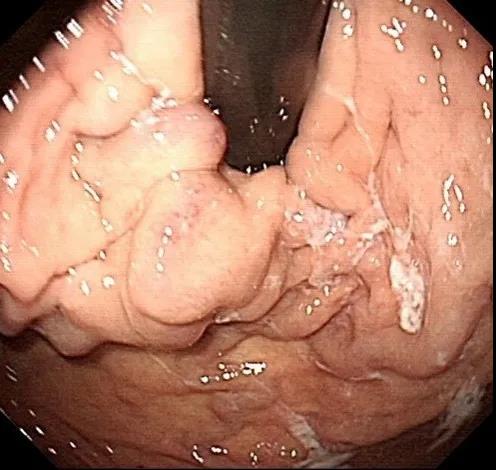

入院后予禁食、抑酸、補液、輸血處理,與家屬溝通,完善胃鏡檢查,結果示胃底巨大曲張靜脈團、門脈高壓性胃病。蓋偉主任考慮胃底靜脈團大、靜脈壓力高,合并分流道的可能性越大,且多數為胃脾分流,應首先完善門靜脈血管成像檢查,以明確血管情況。成像檢查結果符合食管胃底靜脈曲張CT表現,胃底血管部分與脾靜脈相交通。

科室組織術前討論,共同讀片,分析:該患者巨大胃底靜脈曲張存在胃脾分流道,巨大者難以套扎,常規組織膠血管內注射治療易引起異位栓塞。術前CT門脈成像檢查清晰顯示靜脈團的血管走行及血管的出入口大致在胃底的位置,鈦夾夾閉可以先行阻斷或減緩血流,隨后的組織膠治療不易發生異位栓塞。于是,團隊決定采用目前最新的鈦夾限流聯合組織膠栓塞術處理該患者的胃底曲張靜脈。

術前胃鏡及血管成像